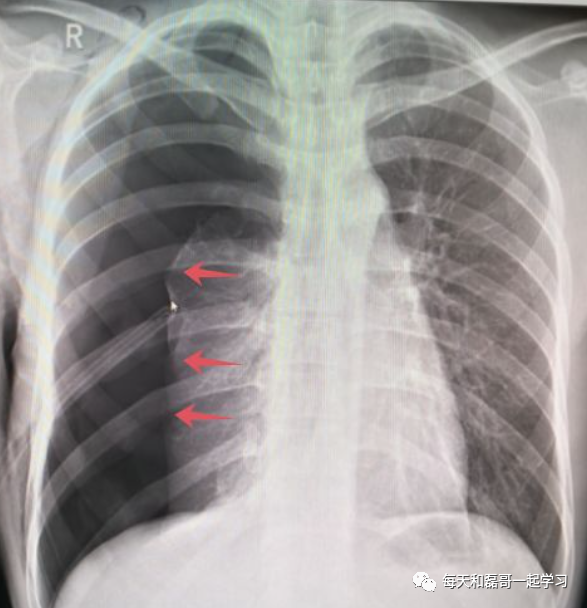

(1)张力性气胸或气胸

气胸患者接受机械通气治疗,易发生张力性气胸,而张力性气胸患者如接受机械通气治疗,则病情会进一步恶化。因此,这类患者在接受机械通气前或同时,须采取胸腔闭式引流,否则可导致患者病情进一步加重。